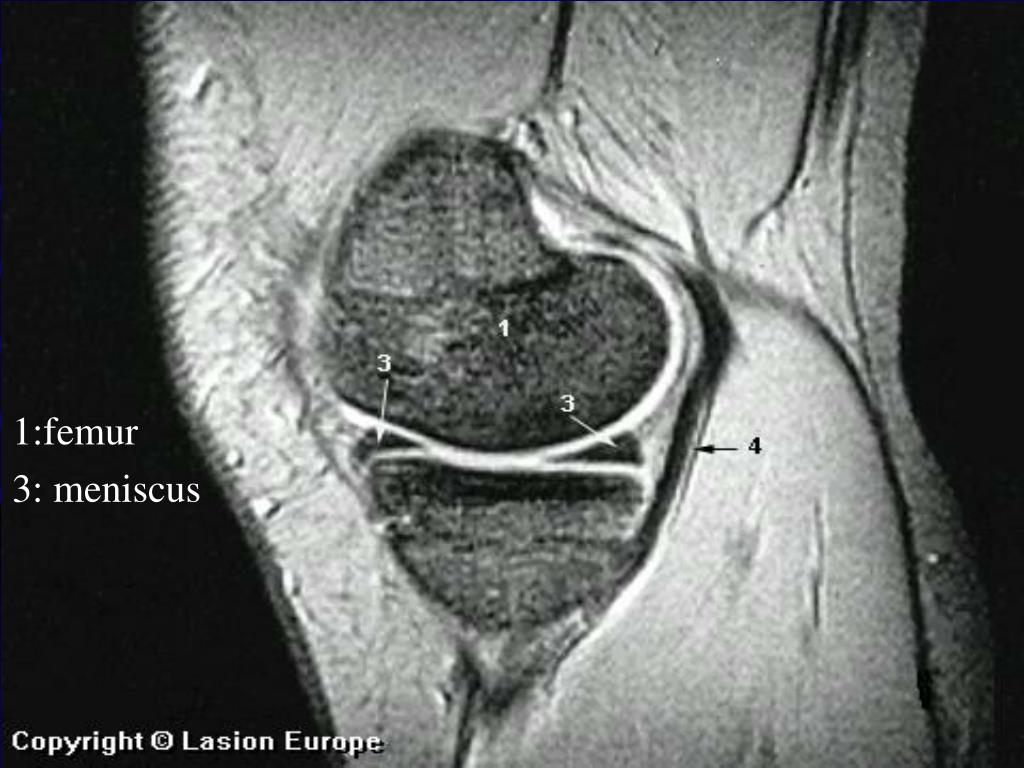

6. 1:femur • 3: meniscus

7. MRI • Het zwarte driehoekje is de meniscus

8. MRI • Als het driehoekje niet volledig zwart is hebben we een meniscusscheur